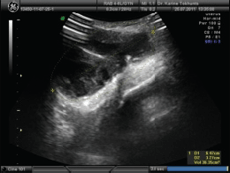

В основном кисту канала Нака дифференцируют с паховой и бедренной грыжами, миомой круглой связки матки, реже проводят дифференциацию с аневризмой сосуда. В большинстве случаев диагностика основывается на данных USI, СТ и IМR. У нашей пациентки мы ограничились проведением USI получена картина многокамерного кистозного образования в толще большой половой губы с резко неоднородным содержимым и множественными фиброзными перетяжками. При цветном допплеровском картировании внутри образования кровоток не получен. В дистальной части левого пахового канала выявляется продолговатая кистозная полость до 2.5 см длиной связанная с вышеописанным многокамерным образованием. Для уточнения диагноза проведен также ретроспективный просмотр видеозаписи диагностической лапароскопии: дистальная часть левой круглой связки и внутрибрюшное отверствие пахового канала были в пределах анатомической нормы. Под спинальным обезболиванием проведено оперативное лечение.